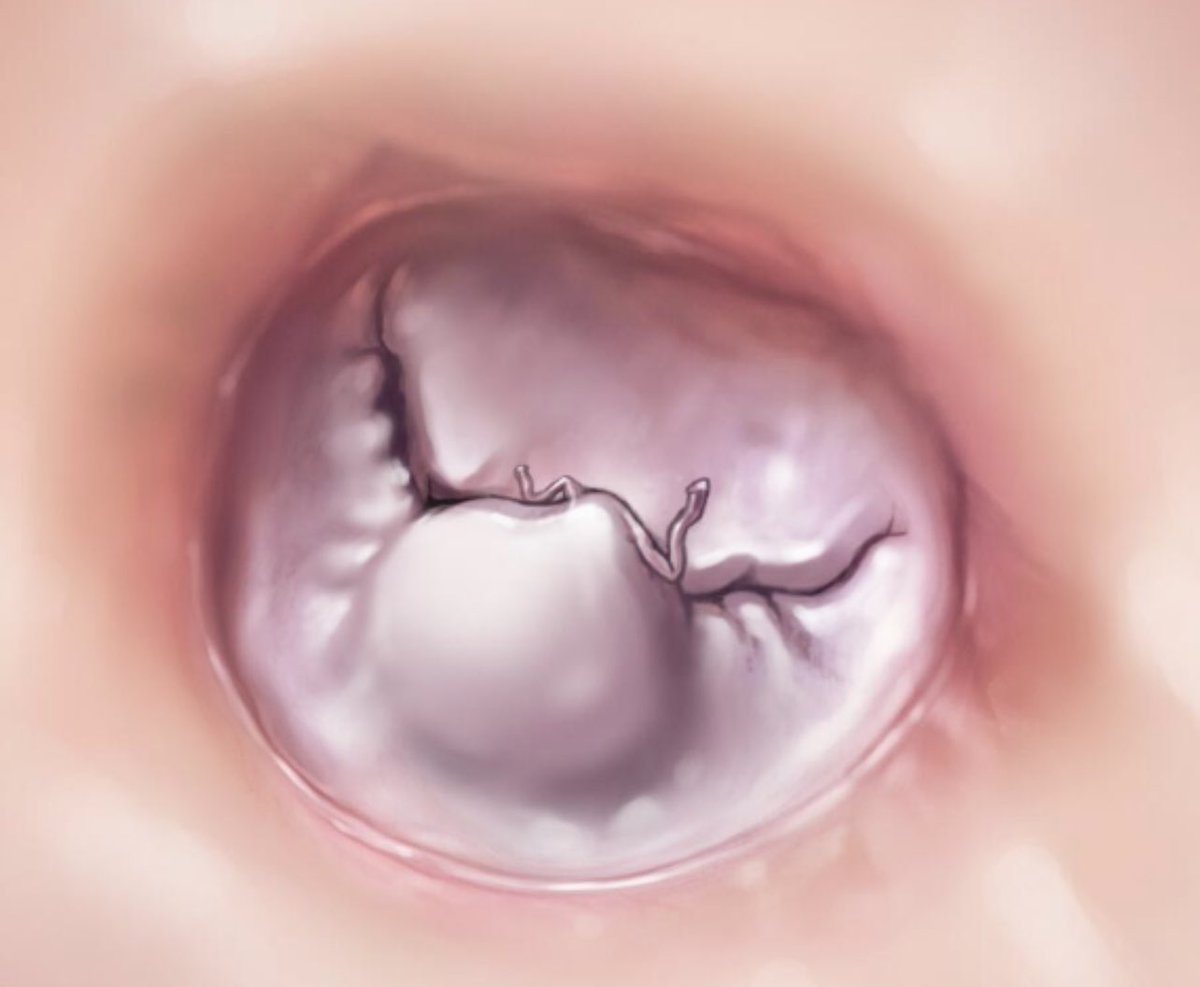

Severe mitral annular calcification. How do you manage this when performing MVR? Debridement with or without patch? Suture around the calcium bar? Suture into the leaflet? Suture to left atrium? Whatever you can to get a good valve in with no perileak.

Aortic valve regurgitation repair in a Bicuspid valve. Plicate (or limited resection) to eliminate conjoined cusp redundancy, close the sub-commissural triangles (5 0 Ethibond with Teflon pledgets) and resuspend the commissures.